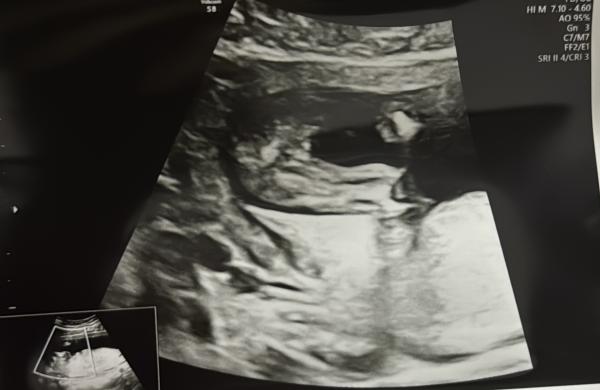

Hali Hallo... laut meine FA ist eine mädchen... ich bin nicht überzeugt was denkt ihr?

Bild zu Mädchen oder Junge - Schwanger - wer noch? Rund um die Schwangerschaft

Wie du bist nicht überzeugt?  Da steht nichts ab, da ist kein Hodensack. Warum sollte es denn dann ein Junge sein? 😅 Es hat die "Typischen 3 Mädchen Linien" links und rechts zwei kleinere und in der Mitte ein Größerer.  Ich sehe es definitiv als Mädchen ❤️

Hallo ! Ich sehe auch ein Mädchen. Die berüchtigte Kaffeebohne ist zu erkennen. Wenn Du natürlich eher davon überzeugt bist das es ein Junge ist, solltest Du evtl. die Ärztin berichtigen  Alles Gute !